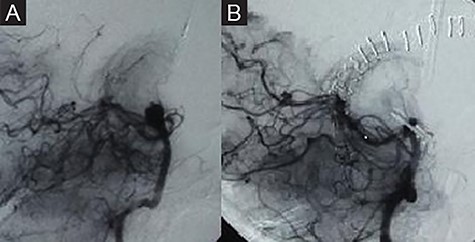

A 52-year-old patient was admitted to our hospital with a subarachnoid hemorrhage Hunt and Hess Grade 4 (Fig. 1). The digital subtraction angiography (DSA) revealed a complex basilar tip aneurysm (Fig. 2A). At the time of patient’s presentation in our clinic, there was no endovascular therapy option in our institution as our hospital lacked a neurointerventional infrastructure. As the optimal timing of surgically treating high-grade aneurysmal subarachnoidal hemorrhage is still controversial and our patient presented with hydrocephalus and a Hunt and Hess Grade 4 subarachnoidal hemorrhage, we first decided to treat the hydrocephalus with placement of an external ventricular drainage. The anatomical location of the aneurysm in the narrow space of interpeduncular fossa filled with blood clots and the severe brain edema were additional factors to the poor initial clinical presentation of the patient that made us decide for a delayed surgical treatment. Under intensive care therapy and treatment of the hydrocephalus with the external ventricular drainage, the clinical situation of the patient improved to Hunt and Hess Grade 3 preoperatively. We decided to clip the aneurysm under hypothermia and temporarycardiac arrest as the wide neck of the aneurysm, its large size and the narrow surgical space could not ensure the safe preparation of the aneurysm neck and the surrounding vessels and would also require a prolonged temporary clip application with increased ischemia risk if a technique with temporarily deflating the aneurysmal sac and allowing comfortable surgical maneuvres was not used. We conducted a thorough preoperative cardiological evaluation that revealed no contraindication for application of extracorporeal circulation using the heart–lung-machine. The operation took place 14 days after the rupture of the aneurysm. The surgical approach was done via a right-sided pterional craniotomy combined with orbitozygomatic osteotomy. Then, the sylvian fissure was opened; subsequently, the Liliequist membrane was opened through the optico-carotid cistern revealing the aneurysm. Following, a sternotomy and opening of the pericardium was performed by our cardiac surgeons. After intravenous administration of 35 000 IU heparin, an aortic and venous cannula was placed. The patient then was put on extracorporeal circulation with the use of heart–lung-machine and was cooled gradually down to 18°C (Fig. 3). At this point, a circulatory arrest was caused by stopping the heart–lung-machine. Simultaneously, the head of the operating table was elevated to promote emptying the blood from the aneurysm sac. Thanks to these manipulations, an efficient and comfortable microsurgical preparation of the aneurysm and its neck from the surrounding small perforating arteries and the proximal branches of the basilar artery was achieved. Hereafter, a clip was placed uneventfully occluding the aneurysm. We gradually rewarmed the patient up to 36.5°C in the following 15 minutes. After administration of protamine sulfate to antagonize the previously administered heparin, the surgery proceeded with the closure of the craniotomy and the thoracotomy. No postoperative complications were recorded and the patient was able to exit the intensive care unit in 8 weeks. A postoperative DSA confirmed the complete occlusion of the aneurysm (Fig. 2B). The patient was transferred 18 weeks after the operation with no focal neurological deficits at the referring hospital.

Preoperative DSA showing a complex basilar tip aneurysm (A). Complete occlusion of the aneurysm in the postoperative DSA (B).